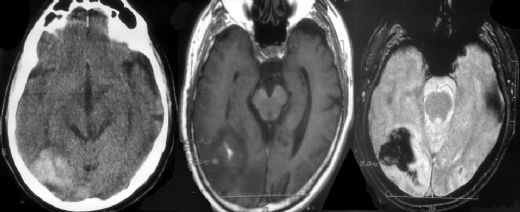

Çocuklarda beyin kanaması, çeşitli nedenlerle meydana gelebilen ciddi bir sağlık sorunudur. Bu durum, çocukların beyin dokusunun zarar görmesine ve yaşamı tehdit eden komplikasyonların ortaya çıkmasına yol açabilir. Beyin kanaması, kafatası içindeki kan damarlarının yırtılması veya sızdırması sonucu meydana gelir ve belirtileri, kanamanın türüne, yerine ve şiddetine bağlı olarak değişiklik gösterir. Beyin Kanaması Türleri Beyin kanamaları, çeşitli tiplere ayrılmaktadır. Bu türler arasında en yaygın olanları şunlardır:

Travmalar, çocuklarda en sık görülen beyin kanaması nedenidir ve bu nedenle çocukların güvenliğini sağlamak oldukça önemlidir. Tedavi Yöntemleri Beyin kanamasının tedavisi, kanamanın türüne, yerine ve çocuğun genel sağlık durumuna bağlı olarak değişiklik göstermektedir. Tedavi yöntemleri şunları içerebilir:

Sonuç Çocuklarda beyin kanaması, ciddi sağlık problemlerine yol açabilen bir durumdur. Belirtilerinin doğru bir şekilde tanınması ve erken müdahale, çocukların sağlığını korumak açısından hayati öneme sahiptir. Ailelerin, çocuklarının güvenliğini sağlamak için gerekli önlemleri almaları ve herhangi bir şüpheli durumda derhal tıbbi yardım almaları önerilmektedir. Ayrıca, çocuklarda beyin kanaması riskini azaltmak için düzenli sağlık kontrollerinin yapılması ve uygun sağlık hizmetlerine erişimin sağlanması önemlidir. |